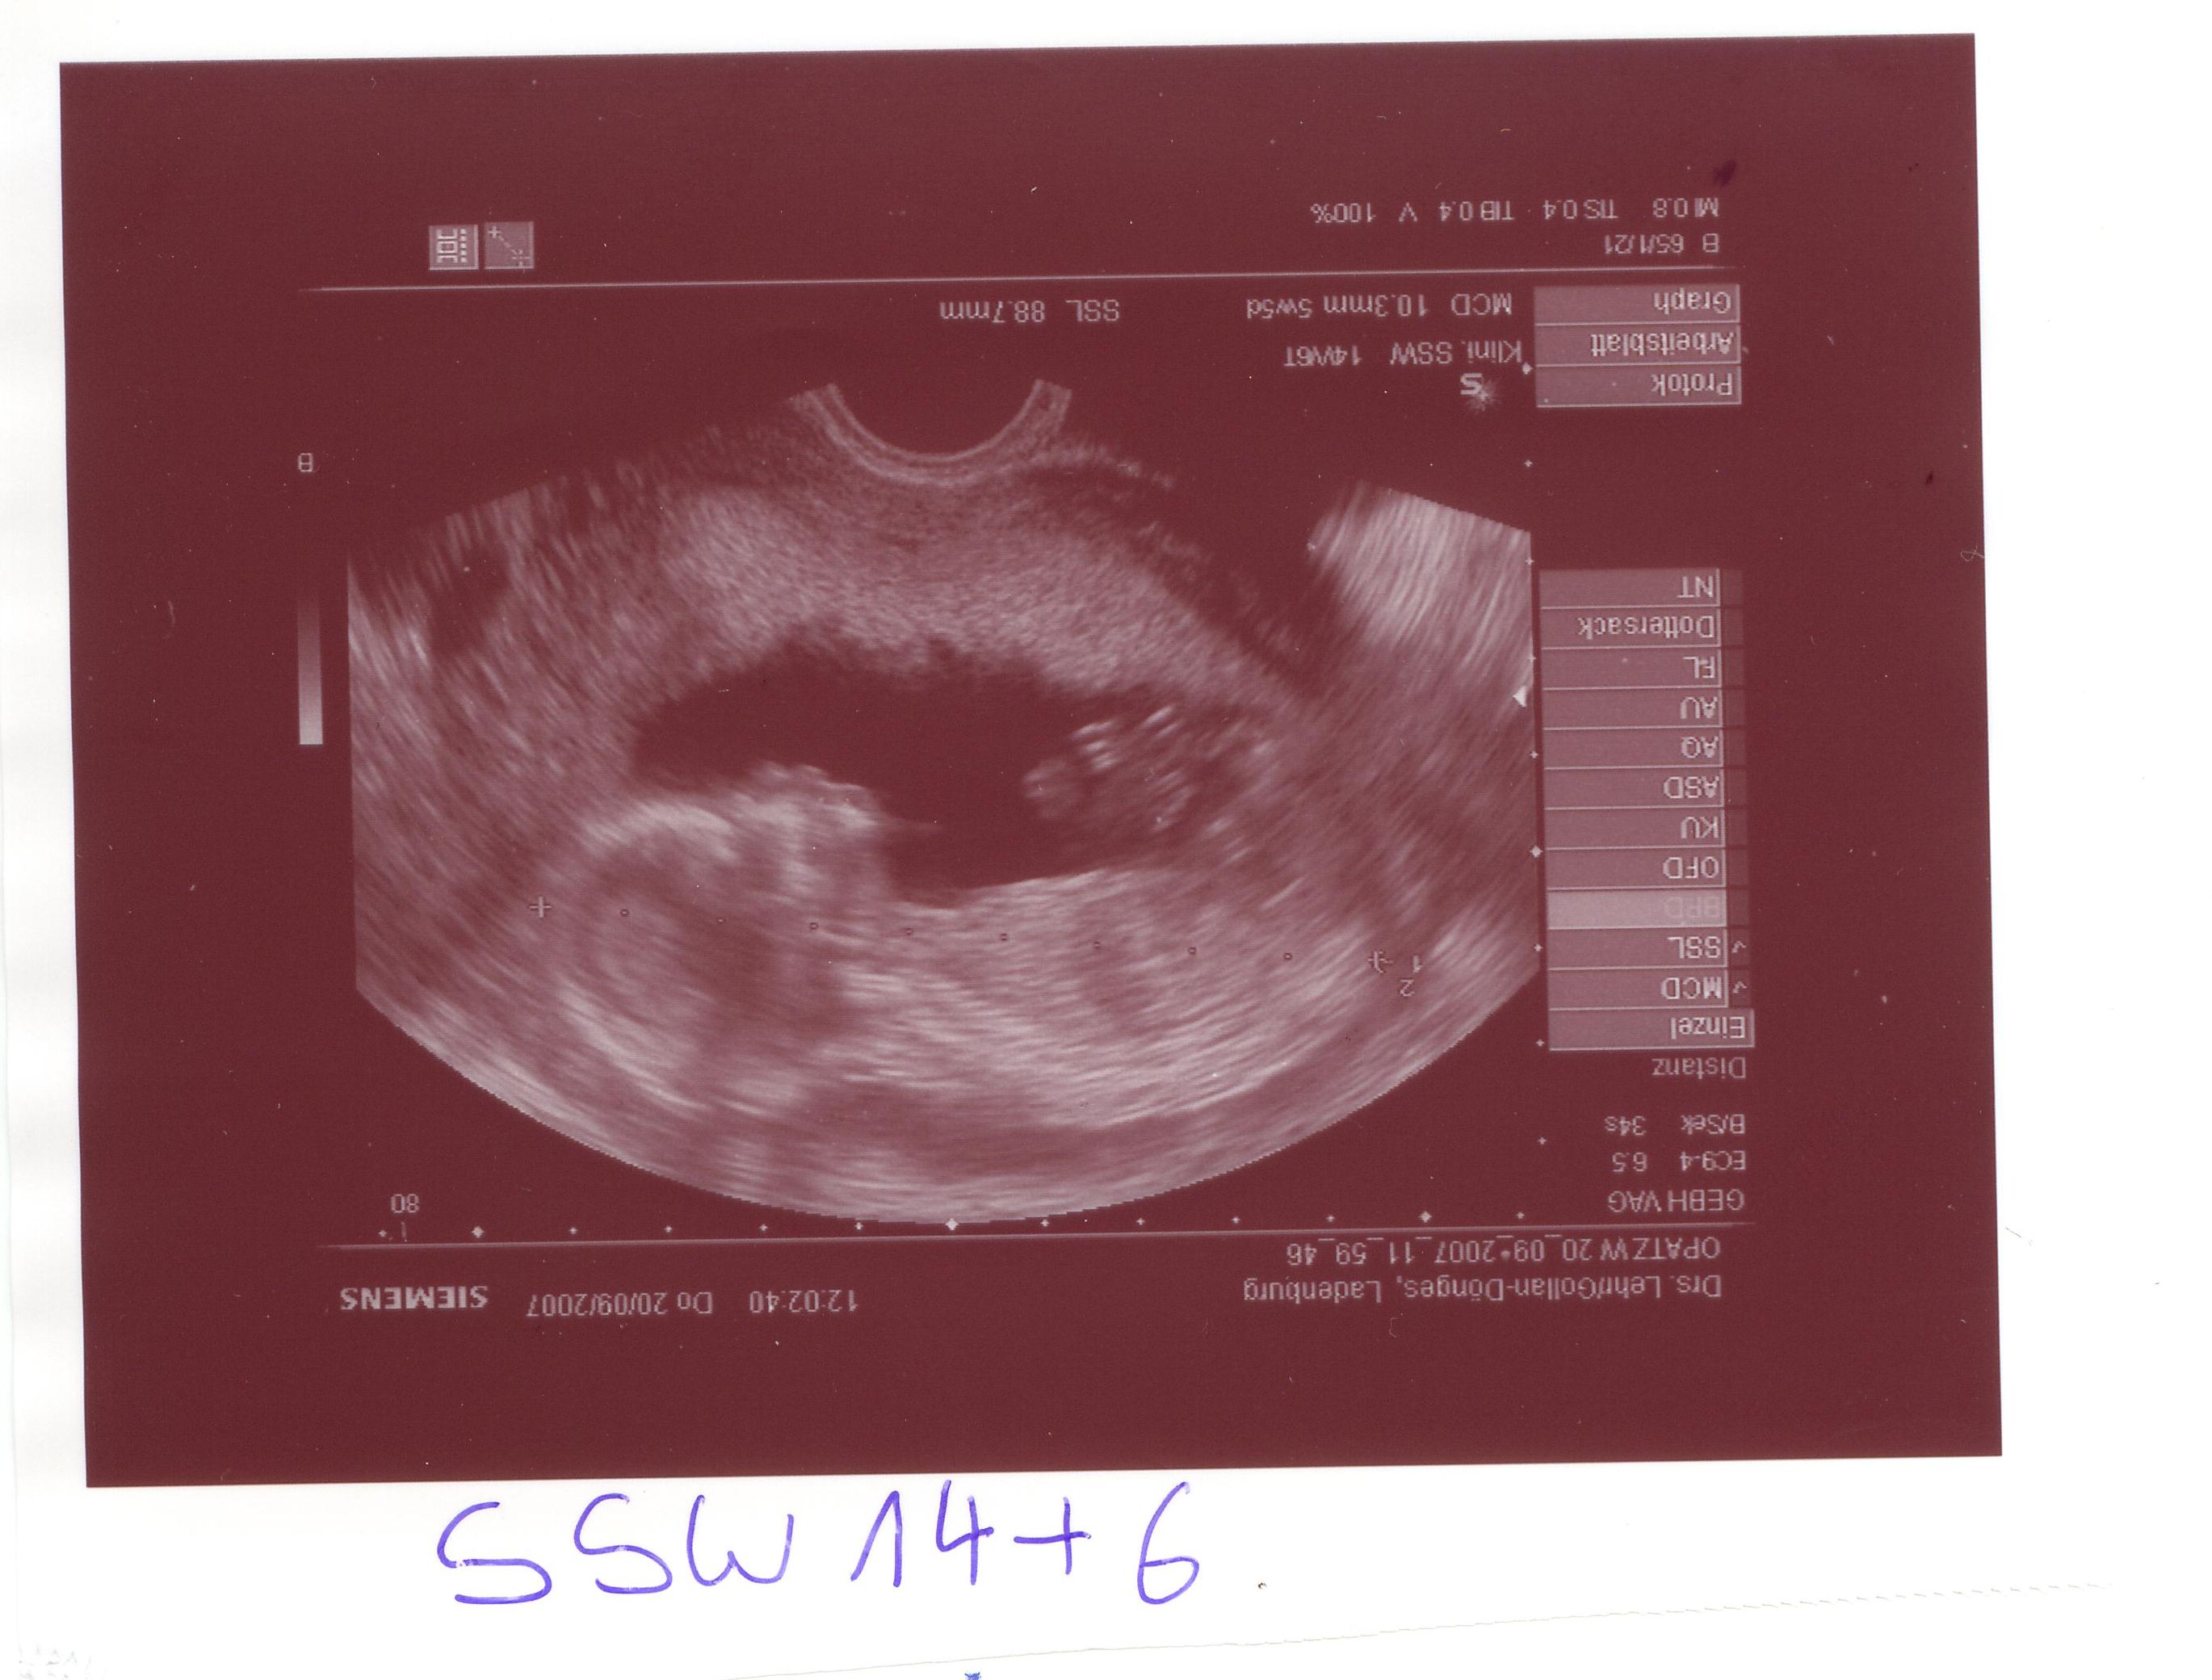

Naja endlich kam dann der US und zum Glück mit unserem Knödel ist alles OK ! Schön gewachsen auf 8,87cm und ganz eingekuschelt in meiner GM lag er/sie, da meinte meine FÄ dass Sie das Baby in dieser Lage leider nicht messen kann und SCHWUPS hat sich unser Knödel ganz genüsslich gestreckt und wir konnten schön messen.

Knödel  SSW 14+6.JPG

Ach so unser Knödel wollte euch auch mal winken

Knödelhand  SSW 14+6.JPG